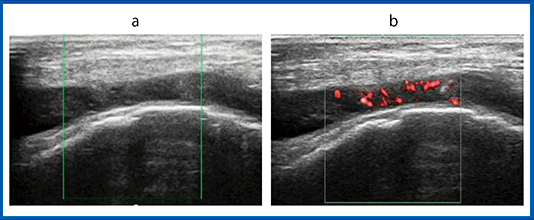

症例2は,右足拇指MTP関節の滑膜炎である。パワードプラ画像で血流信号を確認でき,SMI画像でも豊富な血流信号が検出できている(図3)。しかし,パワードプラ画像は浅部の血流信号は描出されているが,深部の血流信号は不十分である。対して,SMI画像は,深部の血流信号も明瞭に描出され,高い感度で検出できている。

図3 症例2:右足拇指MTP関節の滑膜炎

a:パワードプラ画像 b:SMI画像